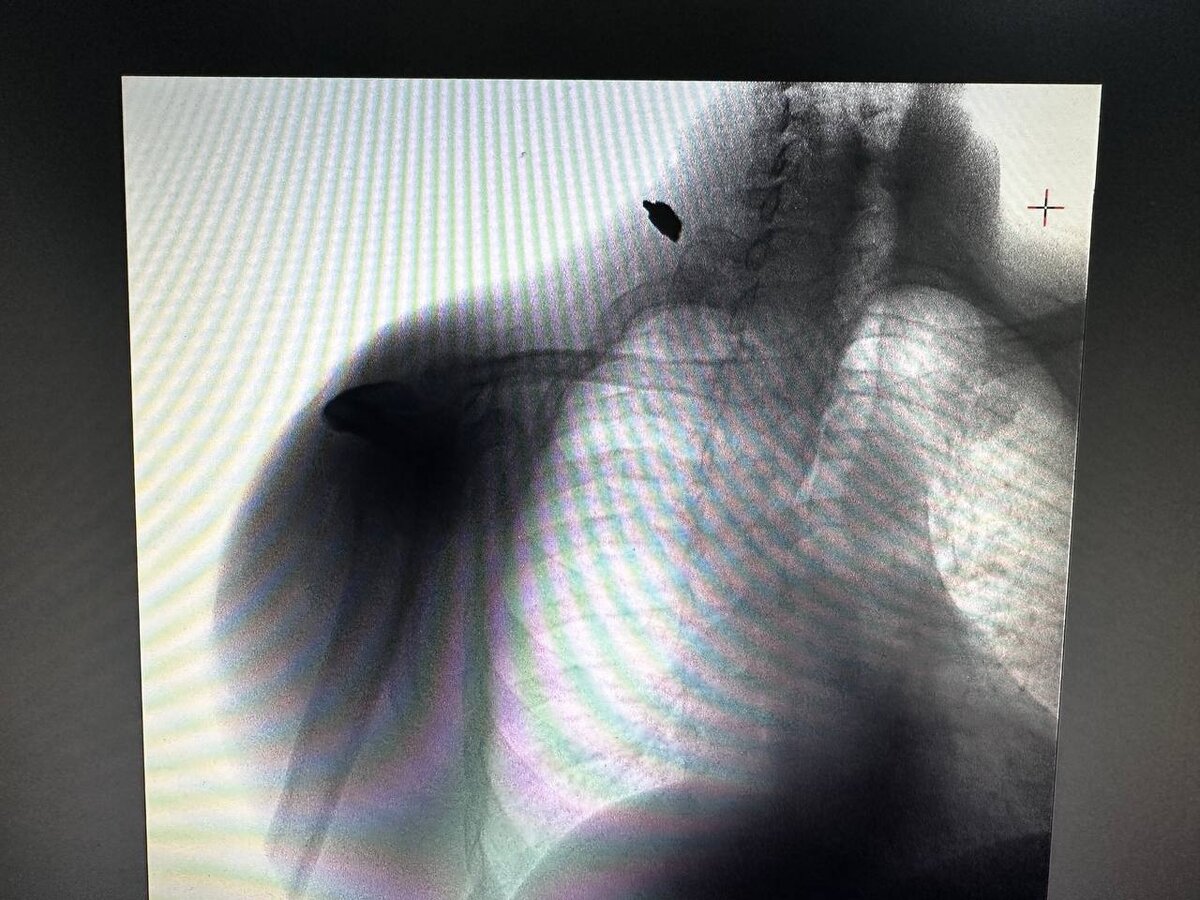

«Мужчина был доставлен в медучреждение в состоянии средней степени тяжести. Мы осмотрели пациента в нашем передвижном мобильном флюорографе и обнаружили осколок», — рассказал руководитель сводного мобильного медицинского отряда ФМБА России Александр Бойков.